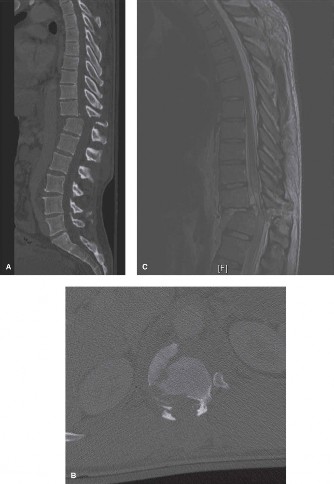

When surgical intervention becomes unavoidable, meticulous pre-operative planning is the cornerstone of a successful outcome. Advanced imaging is non-negotiable. An MRI with and without gadolinium contrast is the gold standard for defining the extent of the epidural abscess, the degree of neural compression, and the involvement of adjacent paraspinal musculature (e.g., psoas abscess). T1-weighted images typically show hypointense signals in the infected marrow, while T2-weighted and STIR sequences reveal hyperintense fluid and edema in the disc space and vertebral bodies. Gadolinium enhancement highlights the vascularized inflammatory phlegmon and the capsule of any abscesses.

In addition to MRI, a fine-cut computed tomography (CT) scan is essential for evaluating bony destruction. CT allows the surgeon to assess bone stock for pedicle screw purchase and to template the size of the interbody cages required for anterior column reconstruction. Upright standing radiographs (if the patient can tolerate them) or full-length supine films are necessary to evaluate global spinal alignment and regional kyphosis.